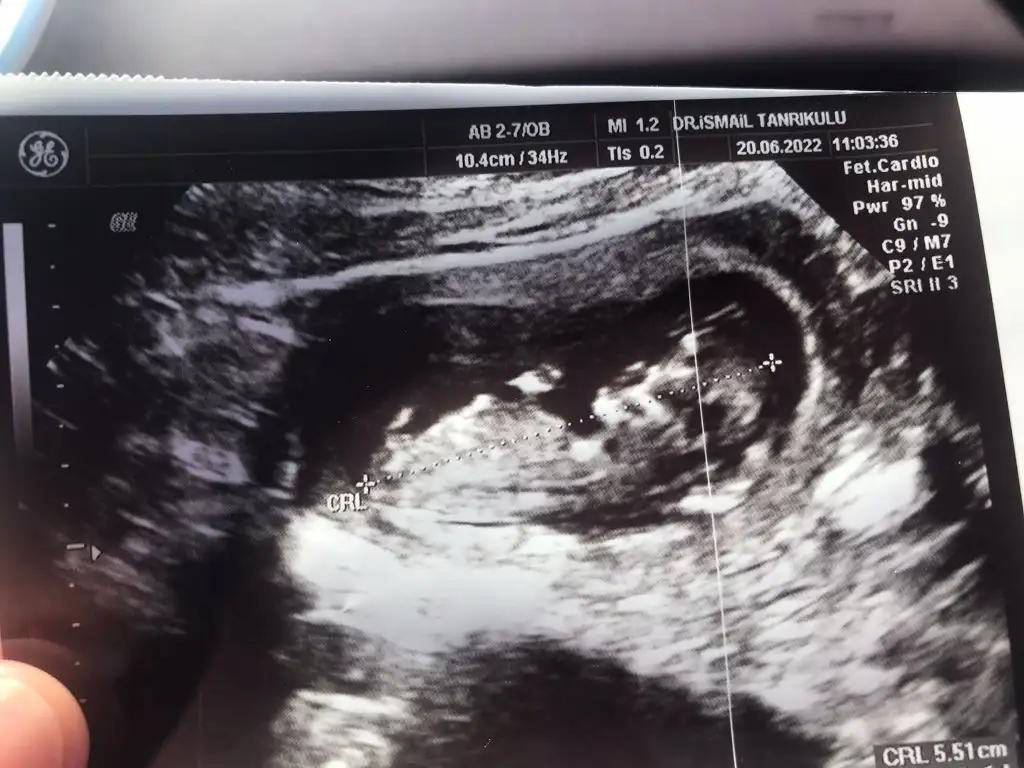

selam canım benimkinide yorumlarmısın?

8+2karından

• 16563189552132089440704.webp

16563189552132089440704.webp

18 KB · Görüntüleme: 45